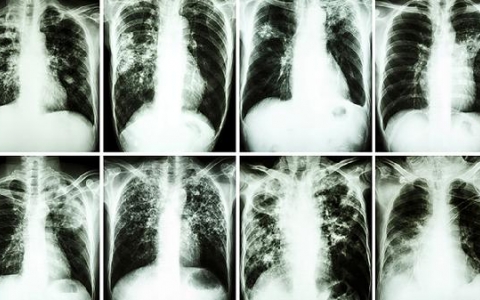

转院后还需要做痰培养么

转院后是否需要进行痰培养检查,主要取决于患者的具体病情和身体状况。如果病情较轻且患者身体素质较好,通常不需要进行痰培养;但如果病情严重,身体素质较差,则可能需要